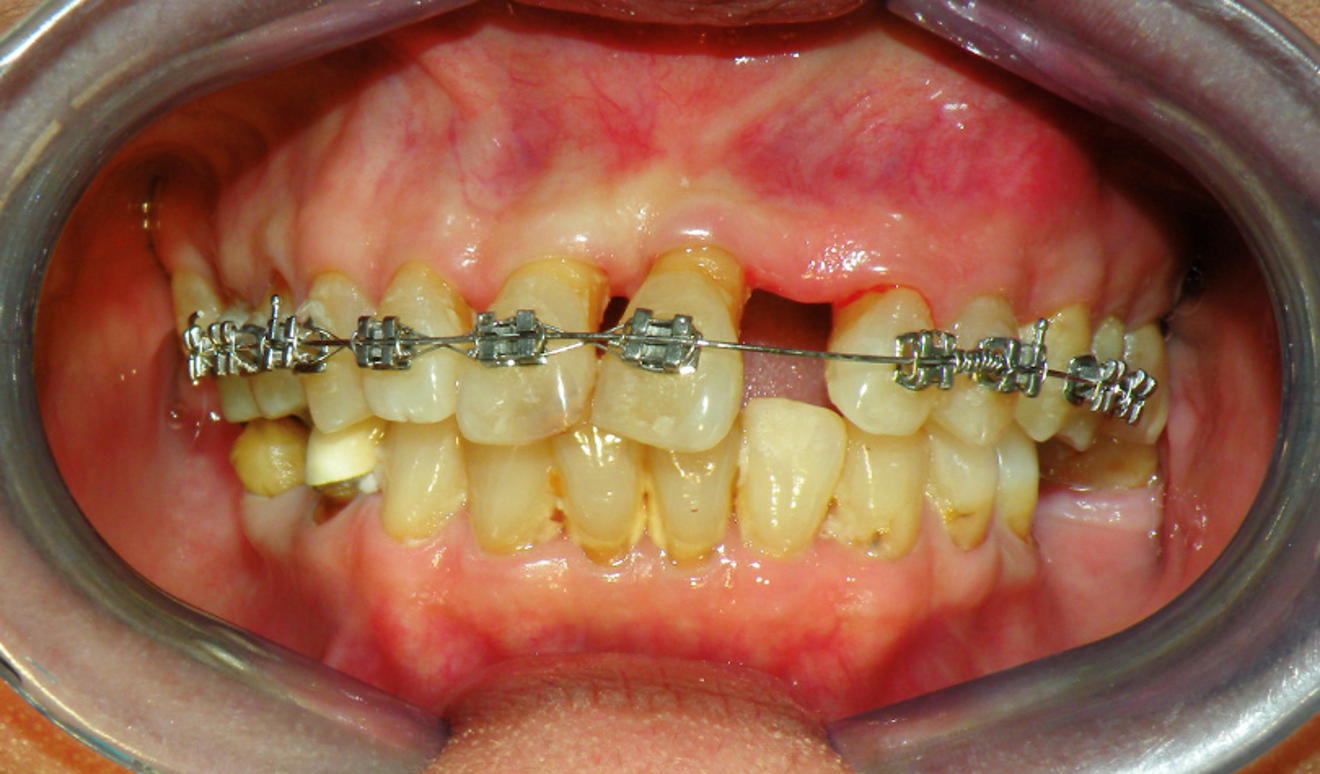

Fig. 12a: Lower arch bonded first to collapse in pursue of overjet and overbite.

Fig 12b:  Upper arch bonded once spaces in lower arch managed.

In case 1, further failure of other remaining teeth occurred over the years due to poor oral hygiene and care. Nevertheless, contact points between upper anteriors from canine to canine remain intact with minimal change to occlusion. However, in case 2, although anteriorly the contact points too remained intact, anterior open bite developed over the years.

Few differences worth mentioning between the two that may indicate reason for non-identical outcome. Although both presented with Class II skeletal pattern, case 1 had a large mandibular length while case 2 had a short mandible. Case 1 had limited diastema present while case 2 had multiple sites including in the lower arch. During speech recorded on video (and displayed through screenshot as shown above), tongue thrusting is visible in case 2. Soft tissues such as the lips, cheeks and tongue affect tooth position and play important roles in dental arch formation and maintenance (Tomes, 1873). Short mandibular length in case 2 may promote towards pseudo macroglossia. Pseudo macroglossia symptoms includes condition in which tongue of normal size but large in relation to adjacent anatomical structures (1). Large and protruding tongue affect the occlusal stability post orthodontic treatment.

Another significant difference would be the single arch approach in case 1. Lower arch was not disturbed and upper arch were moved to accommodate to it. However, in case 2, anterior segment in the lower arch was collapsed to create overjet and overbite. The lower anterior teeth have been shown to be the most prone to relapse with 40-90% rate 10 years post orthodontic treatment (2). Natural changes to the dental arches that occur during aging and maturation are known to contribute to the problem of posttreatment relapse, particularly decreases to arch length and intercanine width. In case 2, intercanine width was reduced during arch collapse with elastomeric powerchain. Retention appears to be better when lower anterior teeth is left alone as presented in case 1.